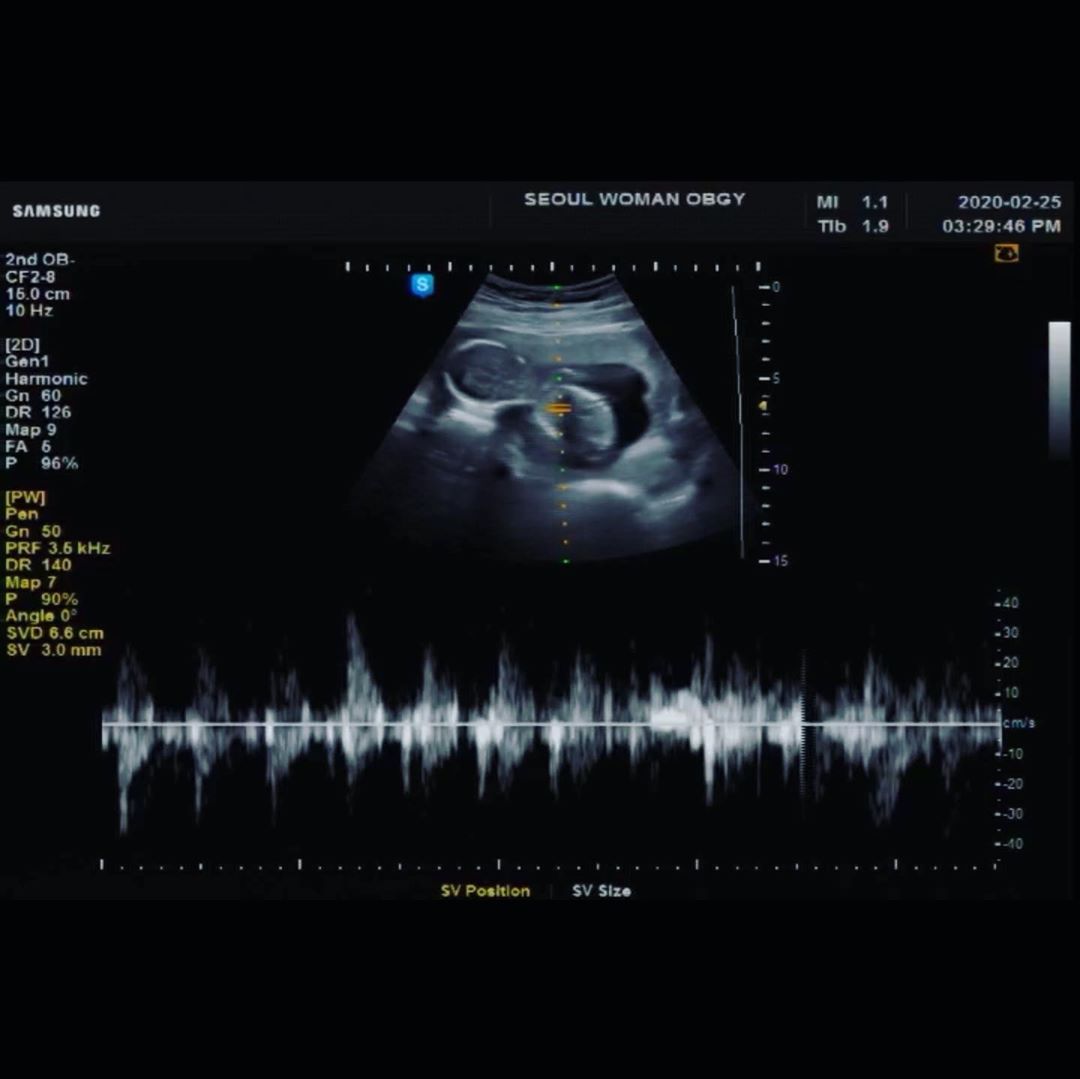

具荷拉的哥哥具浩仁日前在IG發文寫下,「今天是結婚二周年紀念日,也是我們書賢(具荷拉的嫂嫂,서현音譯)的生日,我的妹妹曾因為很盼望能抱姪兒,總是買了保健食品給嫂嫂,妳曾說會為第一個寶貝做到一切,還曾說過要送他上大學的我的妹妹。」並曬出一張超音波照,透露妻子懷孕喜訊。

具浩仁透露,具荷拉入殮那天,他曾對妹妹許願「下輩子來當我女兒吧」,沒想到如今2個月後妻子真的懷孕,寶寶性別也被檢查出是女孩,夫妻倆也祈求:「名字就取妳說過很好聽的荷琳,請守護姪女順利出生並健康長大吧。」最後他仍舊難忍悲傷表示:「如果早一周知道這件事情,會不會就不會發生這種事了呢?對不起,好想妳…。」讓粉絲看了忍不住淚崩。